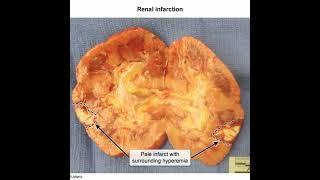

ল্যাবের যন্ত্রাংশ চুরি, চিকিৎসা অব্যবস্থাপনায় ভোগান্তি | Corona Virus | Covid 19 | Corona Infarct

EKHON TV